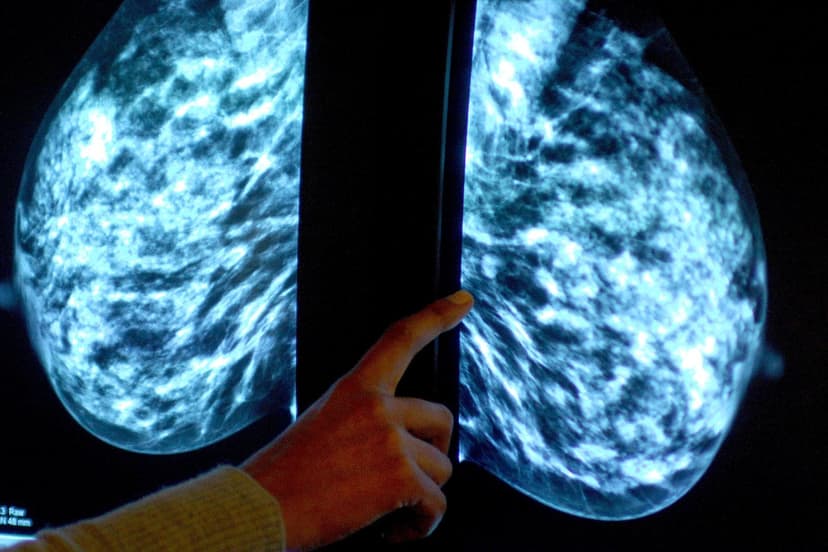

Groundbreaking results from Roche's Phase III lidERA trial reveal that its experimental oral drug, giredestrant, achieved a 30% reduction in breast cancer recurrence compared to standard endocrine therapy. This significant advancement offers new hope for patients battling estrogen-receptor-positive breast cancer, a form accounting for approximately 70% of all cases.

The trial data indicates that after three years, an impressive 92.4% of patients on giredestrant remained alive and disease-free. This contrasts with the 89.6% seen in the standard-of-care group, highlighting giredestrant's potent efficacy. The drug belongs to a novel class of oral selective estrogen receptor degraders (SERDs) designed to combat hormone-driven tumors.

With a favorable safety profile and potential to become a new standard in adjuvant endocrine therapy, giredestrant is poised to address a critical unmet need. Despite existing treatments, a notable portion of early-stage patients still face recurrence, making this breakthrough particularly impactful. Roche anticipates significant revenue generation from this promising oncology development.